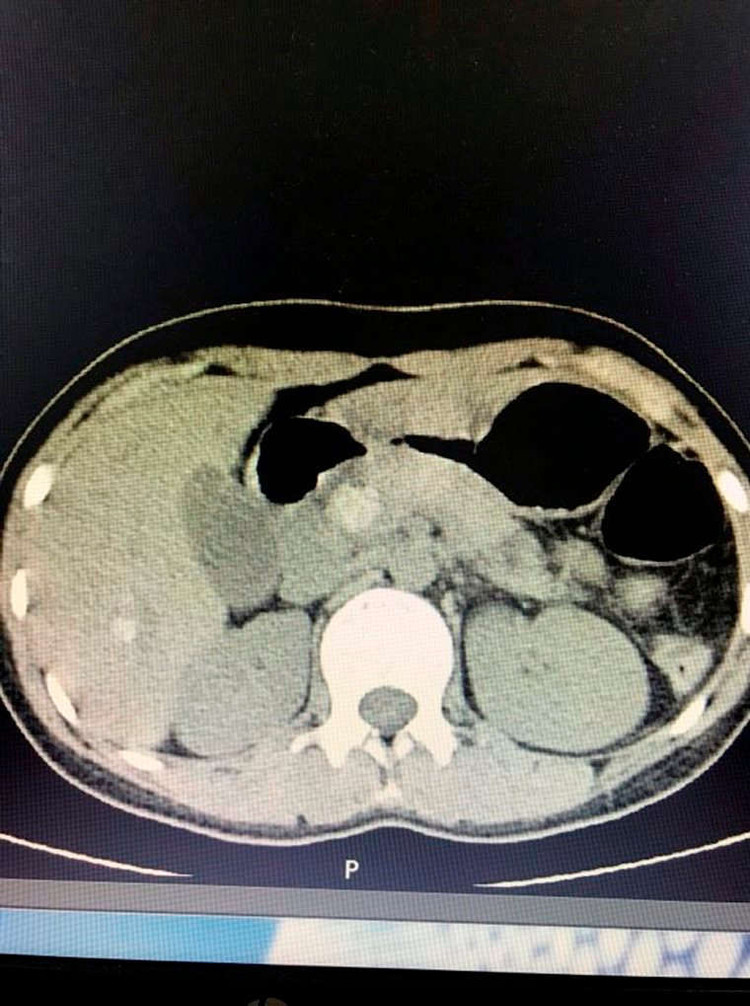

Sau khi được siêu âm và chụp cắt lớp, cho thấy hình ảnh sỏi ống mật chủ và sỏi đường mật trong gan phải. Người bệnh nhanh chóng được điều trị nội khoa, hồi sức tích cực và chỉ định phẫu thuật mở ống mật chủ lấy sỏi, nội soi đường mật tán sỏi điện thủy lực.

Theo ThS.BS Trần Thanh Tùng  - Phó trưởng Đơn vị Ngoại – Trung tâm KCB CLC, người trực tiếp thực hiện ca phẫu thuật cho biết: Đây là một trong những trường hợp phẫu thuật khó vì sỏi trong gan và sỏi ống mật chủ kích thước tương đối to, đường kính khoảng 2cm nằm kẹt chặt tại vị trí Oddi, không thể lấy sỏi bằng phương pháp thông thường. Các bác sĩ đã phải phẫu thuật mở ống mật chủ lấy sỏi kết hợp với nội soi đường mật tán sỏi điện thủy lực giúp tán nhỏ viên sỏi, thu nhỏ kích thước để lấy sỏi ra ngoài đồng thời không làm tổn thương cơ Oddi.

Viên sỏi to kẹt chặt tại vị trí Oddi